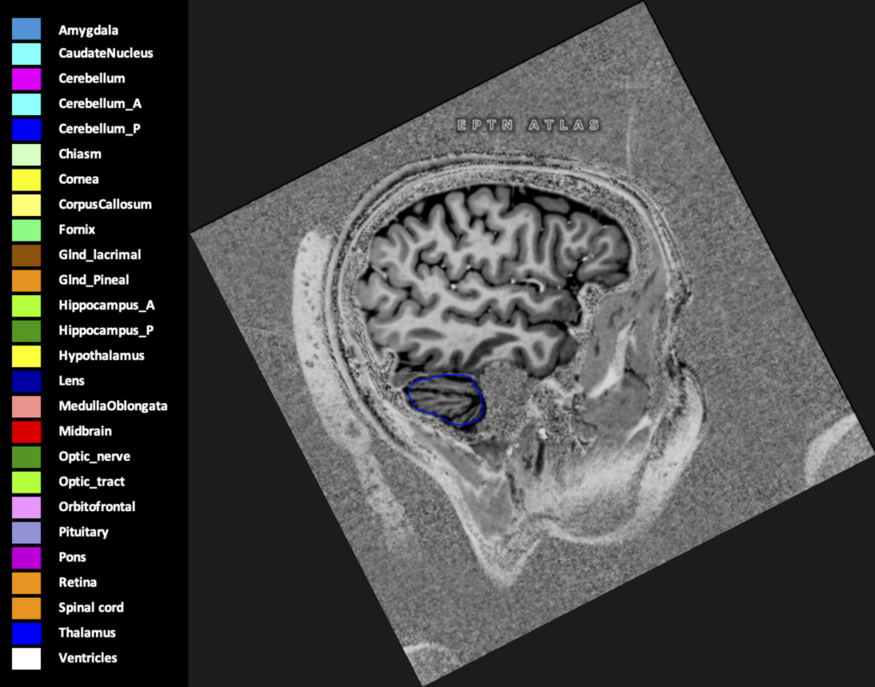

Included are all OARs known to be relevant for radiation-induced toxicity in neuro-oncology: brain, brainstem (midbrain, pons, medulla oblongata), chiasm, cerebellum (anterior & posterior), cochlea, cornea, hippocampus (anterior & posterior), hypothalamus, lens, lacrimal gland, optic nerve, pituitary, skin, and vestibular & semicircular canals. To further facilitate research on cognition, vision and radiological changes after irradiation of the brain, potential clinically-relevant OARs are included: amygdala, caudate nucleus, cerebellum (anterior & posterior), corpus callosum, fornix, macula, optic tract, orbitofrontal cortex, periventricular space (PVS), pineal gland, and thalamus.

Three-dimensional delineation of the 25 consensus OARs for neuro-oncology are shown on CT (WW/WL 120/40, 3000/600), 3T MR images, (T1Gd, T2FLAIR 1mm) and 7T MR (MP2RAGE 0.7 mm). All are presented in transversal, sagittal and coronal view.